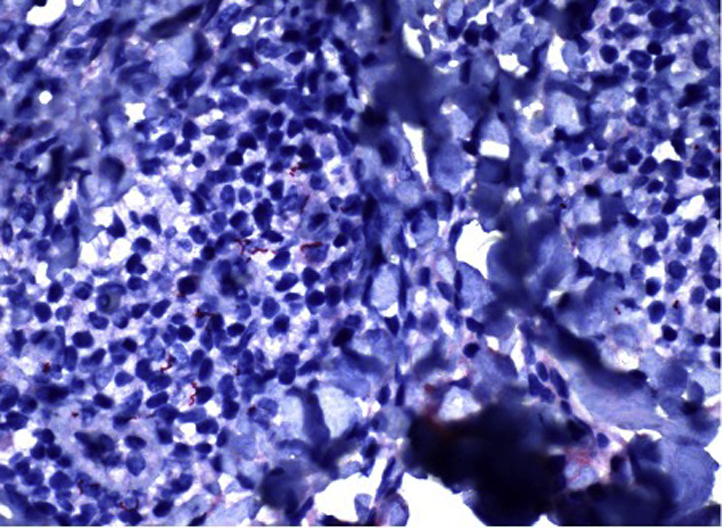

Fig 4.

Spirochetes present in the dermal layer of biopsy specimen submitted for immunohistochemical analysis.